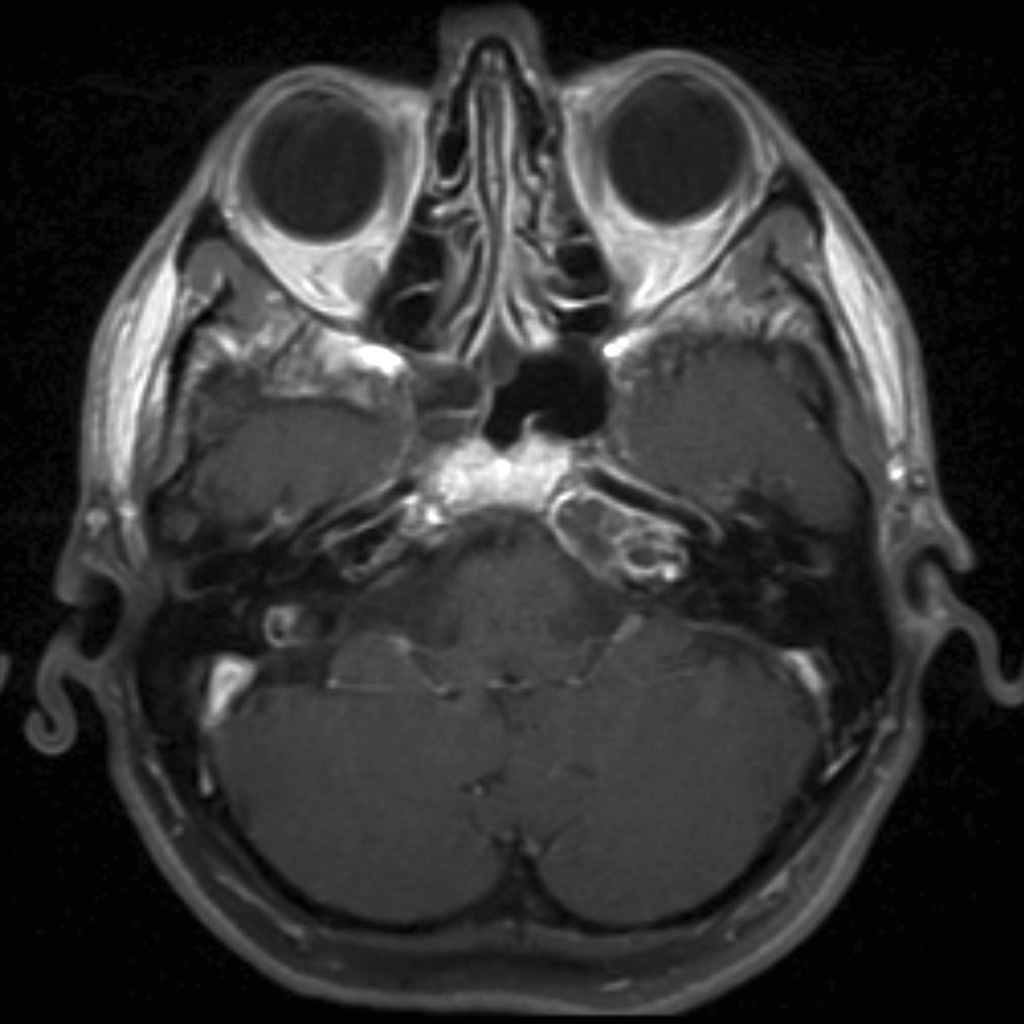

cochlear aplasia

The labyrinth is abnormal with the cochlear absent (cochlear aplasia). The vestibule, semicircular canals and ossicles are present.

Cochlear aplasia, or complete absence of the cochlea is a rare anomaly which accounts for only 3% of cochlear malformations.